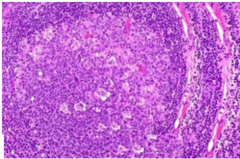

Sarcoidosis

Many non-caseating granulomas throughout the body

Non-caseating granuloma

Lacks central necrosis

Caseating granuloma

-caseous necrosis in the center of the granuloma (one side of Slide). -Zones of epithelioid histiocytes and lymphocytes at the other side surround the caseous material.